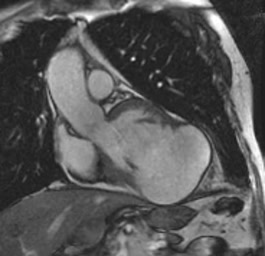

4 camere apicale COLOR. Evidente disfunzione sistolica con texture a "vetro smerigliato. Insufficienza mitralica e tricuspidale.